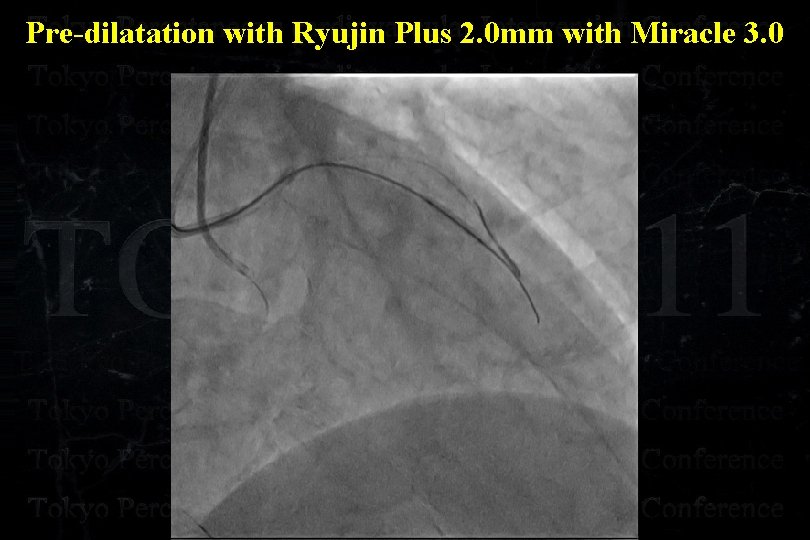

Pre-dilatation with Ryujin Plus 2. 0 mm with Miracle 3. 0